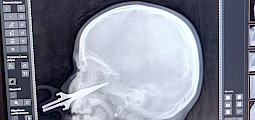

Ошто 5 жашар кыздын бетине сайылып калган кайчыны дарыгерлер алып чыгышты

Ден соолук / 13/03 20:01